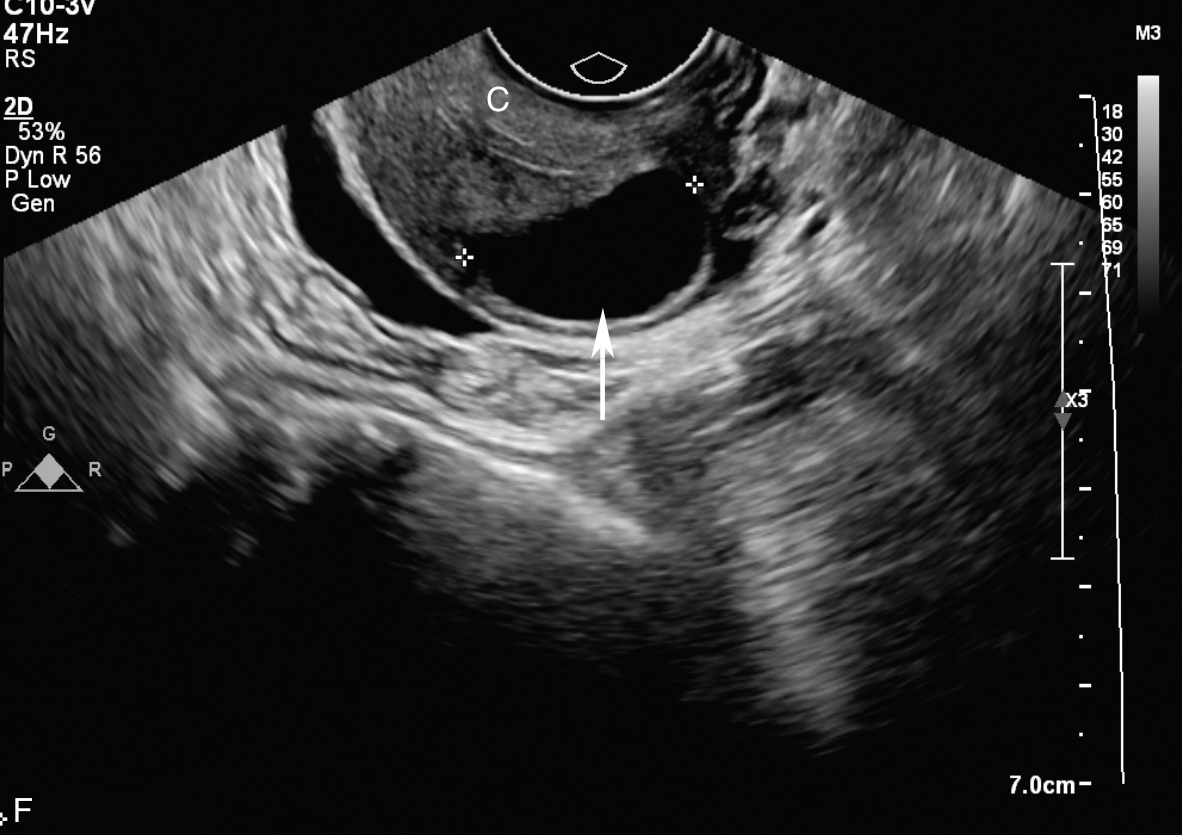

经阴道超声检查见图3-10-1。子宫前位,宫体大小5.6cm×6.9cm×6.5cm,宫腔内查见7.1cm×2.6cm×3.5cm不均质稍强回声,其内回声极不均匀,其内可见多个无回声区,最大无回声区的最大径为0.8cm,周边及其内探及丰富血流信号,该团块与子宫前壁关系密切。宫颈后唇查见囊性占位,大小为2.5cm×1.3cm×1.9cm,囊液清亮,未探及明显血流信号。双附件区未见确切占位。超声检查结果:宫腔内占位,宫颈后唇囊性占位。

图3-10-1 常规超声声像图

A.子宫矢状切面显示宫腔内稍强回声;B.子宫横断面显示宫腔内强回声;C.子宫矢状切面显示宫颈管内占位;D.宫颈管内占位的血流情况;E.宫腔占位的血流情况;F.宫颈囊性占位(箭头所示)。UT:子宫;C:宫颈;MA:肿物。